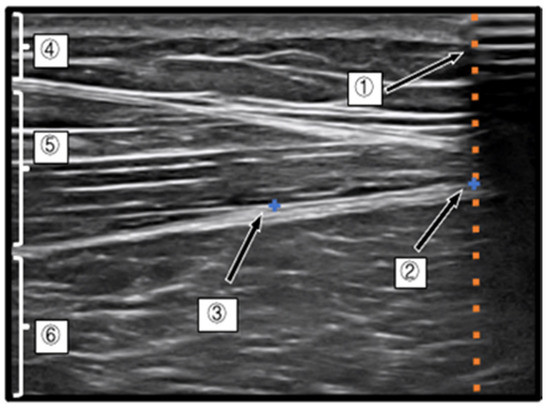

Measurement of the Index Point of the D-Fascia and Calculation of the Movement Distance